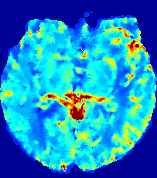

Slice #1Slice #2Slice #3Slice #4Slice #5Slice #6Dgtsuperscript𝐷gtD^{\text{gt}}Refer to captionRefer to captionRefer to captionRefer to captionRefer to captionRefer to caption(a)Refer to captionRefer to captionRefer to captionRefer to captionRefer to captionRefer to caption(b)Refer to captionRefer to captionRefer to captionRefer to captionRefer to captionRefer to caption(c)Refer to captionRefer to captionRefer to captionRefer to captionRefer to captionRefer to caption(d)Refer to captionRefer to captionRefer to captionRefer to captionRefer to captionRefer to caption(e)Refer to captionRefer to captionRefer to captionRefer to captionRefer to captionRefer to caption(f)Refer to captionRefer to captionRefer to captionRefer to captionRefer to captionRefer to captionRefer to caption000.060.060.060.120.120.120.180.180.180.240.240.240.300.300.30(mm2/s)𝑚superscript𝑚2𝑠(mm^{2}/s)

Figure 13: PIANO effectiveness and robustness testing: diffusion imaging via diffusion. Top row shows Dgtsuperscript𝐷gtD^{\text{gt}} used for simulating the ground truth pure diffusion. (a)-(f) refer to the results for D𝐷D estimated from the ground truth pure diffusion image time-series where Rician noise at levels 0%, 2%, 4%, 6%, 8%, 10% was added respectively.

Similarly, starting from the same initial condition C0superscript𝐶0C^{0} as in the ‘Advection Imaging’ experiment for each patient, we simulate concentration time-series {Cti(Ω)|i=0, 1,, 40}conditional-setsuperscript𝐶subscript𝑡𝑖Ω𝑖0140\{C^{t_{i}}\in\mathbb{R}(\Omega)|i=0,\,1,\,\ldots,\,40\} via a diffusion PDE, where we define the ground truth diffusivity D:=Dgtassign𝐷superscript𝐷gtD:=D^{\text{gt}} via the ADC map of the ISLES 2017 training set (ADC values are scaled by 0.000010.000010.00001 to ensure numerical stability):

Note this is likely not a spatially representative ground-truth for perfusion imaging, as it measures different effects from diffusion imaging. However, we still use it as a quasi-realistic pattern of diffusivity in the brain. We also added 2%, 4%, 6%, 8%, 10% levels of Rician noise to obtain simulations of ‘Diffusion Imaging’. The estimated Destsuperscript𝐷estD^{\text{est}} given concentrations of all noise levels for one patient are shown in Fig. 13, PIANO estimation results for all patients are summarized in Fig. 11 (b). Again, PIANO demonstrates its capability to recover the underlying diffusion field. In Fig. 13, when the noise level is increasing, some noisy patterns indeed appear in the associated Destsuperscript𝐷estD^{\text{est}}. Note that the ground truth diffusivity applied in this simulation experiment is about ten times larger than the diffusivity estimated in reality (Fig. 3, Fig. 4).